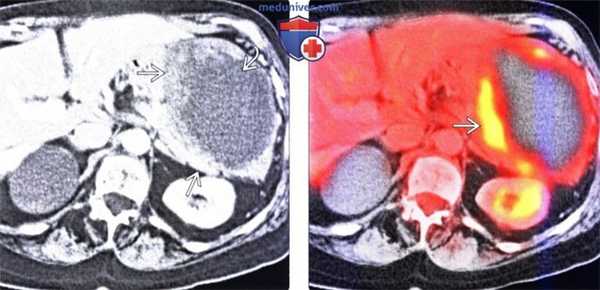

(Слева) На аксиальной КТ с контрастным усилением определяется большая экзофитная гастроинтестинальная стромальная опухоль (ГИСО), возникшая в области большой кривизны желудка. Опухоль имеет толстую стенку, слегка усиливающуюся при контрастировании, в центре опухоли находится зона некроза.

(Справа) При комбинированной ПЭТ/КТ у этого же пациента определяется зона повышенного захвата ФДГ в солидной части образования. ПЭТ с ФДГ позволяет определить активность в первичной опухоли, также является средством обнаружения метастазов. Кроме того, метод позволяет оценить ранние изменения, возникшие в ответ на терапию, прежде чем будут обнаружены морфологические изменения со стороны опухоли.